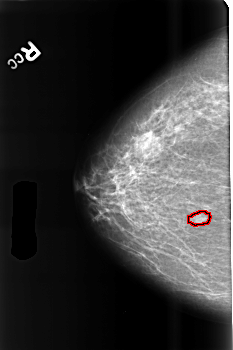

B_3458_1.RIGHT_CC

RIGHT_CC LINES 4544 PIXELS_PER_LINE 3024 BITS_PER_PIXEL 12 RESOLUTION 50 OVERLAY

FILE: B_3458_1.RIGHT_CC.OVERLAY

TOTAL_ABNORMALITIES 1

ABNORMALITY 1

LESION_TYPE MASS SHAPE LOBULATED MARGINS CIRCUMSCRIBED-ILL_DEFINED

ASSESSMENT 4

SUBTLETY 4

PATHOLOGY BENIGN

TOTAL_OUTLINES 1

BOUNDARY